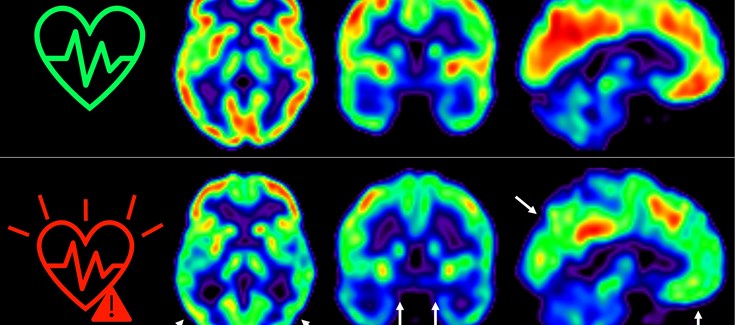

El equipo, liderado por los Drs. Marta Cortés Canteli y Juan Domingo Gispert, ha seguido a estos individuos a lo largo de 5 años y han encontrado que aquellos que mantienen un riesgo cardiovascular elevado durante todo este tiempo sufren una disminución aún mayor del metabolismo cerebral medido a través de técnicas de imagen como tomografía por emisión de positrones (PET).

Hemos detectado un declive metabólico cerebral tres veces mayor que el de personas que se mantienen en bajo riesgo cardiovascular”, señala Catarina Tristão-Pereira, primera firmante del artículo y becaria INPhINIT de la Fundación ”la Caixa.

Además, el equipo descubrió que la progresión de la aterosclerosis subclínica en las carótidas durante estos 5 años se relacionaba con una disminución del metabolismo en regiones cerebrales vulnerables a la enfermedad de Alzheimer, de manera aditiva al efecto de los propios factores de riesgo cardiovascular. “Estos resultados corroboran que la detección por imagen de la aterosclerosis subclínica aporta información muy relevante”, añade el Dr. Fuster, investigador Principal del estudio PESA. “La relación entre el cerebro y el corazón es un tema fascinante y con este estudio hemos visto que empieza mucho antes de lo que se creía”, continúa.